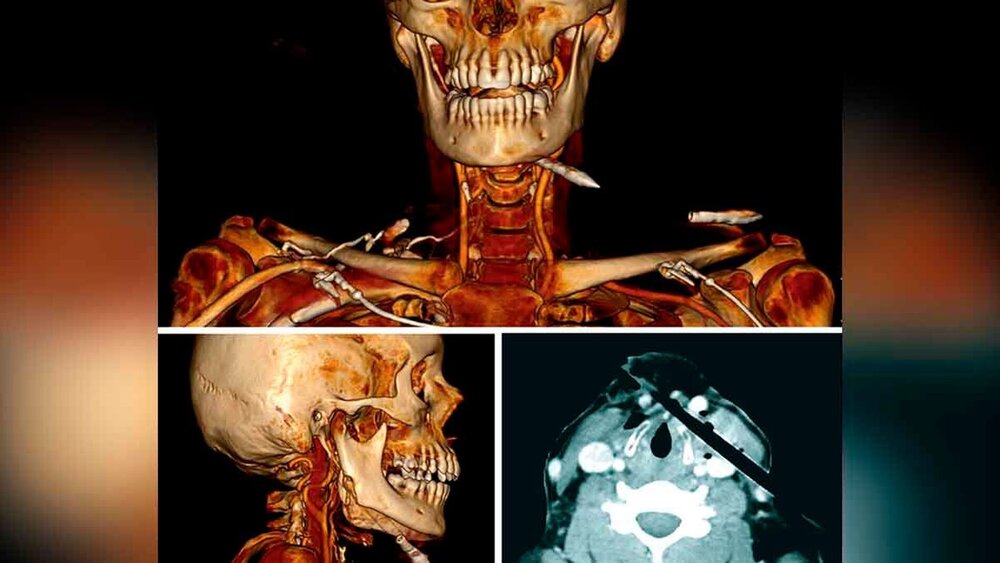

Das Kopf/Hals-CT mit Kontrastmittel zeigte einen kranialen Bolzen mit Eintritt in die rechte Gl. parotidea, Penetration des rechten Ramus mandibulae und Austritt kaudal der linken Mandibula sowie einen kaudalen Bolzen mit Eintritt von anteromedial rechts auf Höhe des Larynx und Austritt im lateralen Halsdreieck links mit Kompression der linken V. jugularis externa. Zudem waren eine Kompression der V. jugularis interna links und ein Weichteilemphysem im Bereich des linken Larynx sichtbar (Abbildung 1). Radiologisch bestand kein Anhalt für eine Verletzung der Trachea oder für einen Pneumothorax. Die begleitende CT-Angiografie erbrachte keinen Hinweis auf größere traumatische Verletzungen der zervikalen Gefäße.

Eine Armbrust ist eine Fernwaffe mit einem Bogensystem, aus dem Bolzen, Pfeile oder Kugeln abgeschossen werden können, indem ein Pistolen-ähnlicher Abzug betätigt wird. Hinsichtlich der Konfiguration der Armbrustbolzen wird zwischen Jagd- und Sport-Bolzen unterschieden. Während Jagdbolzen unterschiedlich konfigurierte, scharfe Breitkopfspitzen aufweisen, die eine letale Blutung beim getroffenen Wild hervorrufen sollen, haben Sportbolzen in der Regel konische Feldspitzen – wie auch im vorliegenden Fall. Der Schaft moderner Armbrustbolzen besteht aus gewichtsparenden Kohlefasern und/oder Kunststoffen (radioluzenter Schaft und radioopake, metallische Spitze im CT – Abbildung 1) [Nowicki et al., 2018; Suematsu et al., 2022].